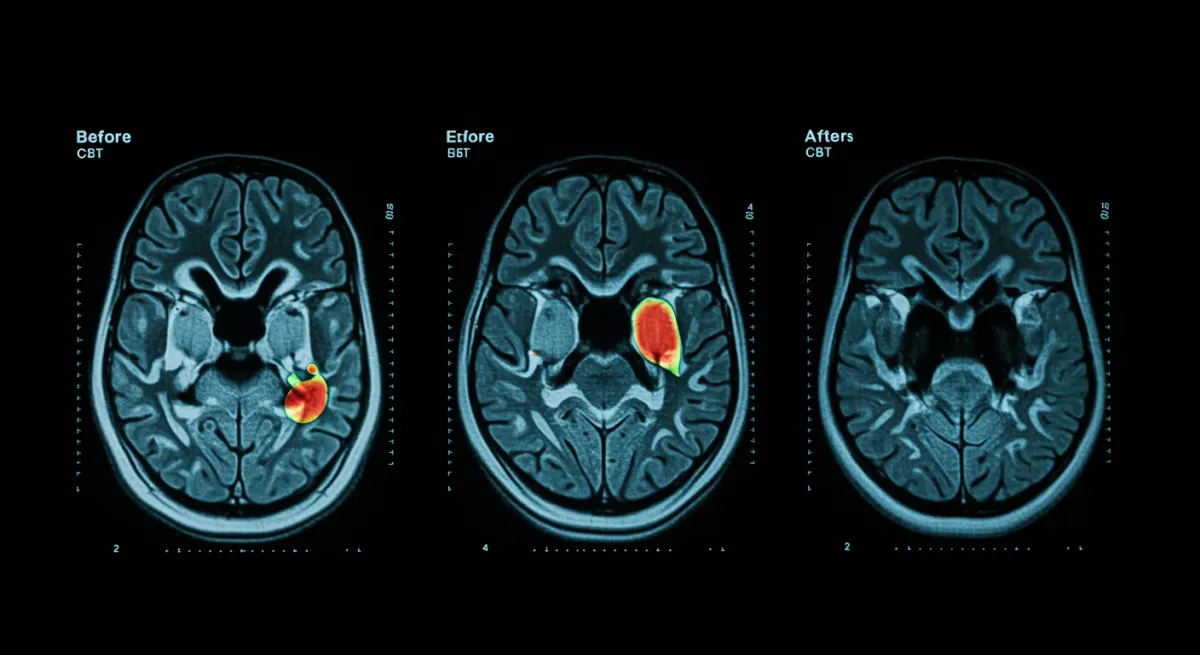

How does CBT change the depressed brain?

Yes. Cognitive behavioral therapy measurably changes brain activity in limbic, striatal, cingulate, and frontal areas, partially normalizing neural patterns associated with depression and reducing negative cognitive biases. A systematic review of 14 task-based fMRI studies published in the Journal of Affective Disorders shows that CBT produces objective, measurable neurobiological changes that correlate with symptom improvement.

This systematic review provides the neurobiological proof that CBT isn’t just “talk therapy” - it’s literally rewiring the brain. The fact that we can see measurable changes in limbic, striatal, cingulate, and frontal areas on fMRI scans is remarkable. These are exactly the brain regions we know are dysfunctional in depression. The limbic system processes emotions, the striatum is involved in motivation and reward, the cingulate cortex handles attention and emotion regulation, and the frontal areas manage executive function and decision-making. CBT is essentially teaching the brain new ways to process information and emotions, and we can now see this happening in real-time through brain imaging.

This systematic review analyzed longitudinal fMRI studies examining brain activity changes in depressive patients undergoing cognitive behavioral therapy. The researchers focused on task-based fMRI studies that measured brain function before and after CBT treatment, allowing them to identify specific neural changes associated with therapeutic improvement. The review examined changes across multiple brain regions and their relationship to symptom remission.

- Understand that CBT produces measurable, objective changes in brain function that can be seen on fMRI scans

- Recognize that CBT works by normalizing abnormal brain activity patterns in key regions involved in emotion and cognition